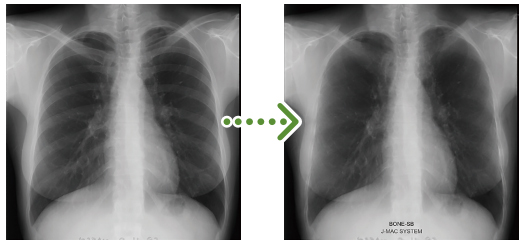

1)肋骨陰影の減弱

撮影した画像データから,AIを用いて肋骨の陰影を薄くする画像処理を行うことで,肺野内の骨に重なった病変の見落としを防ぎます。